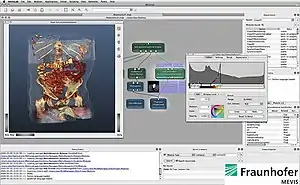

MeVisLab is a cross-platform application framework for medical image processing and scientific visualization. It includes advanced algorithms for image registration, segmentation, and quantitative morphological and functional image analysis. An IDE for graphical programming and rapid user interface prototyping is available.

MeVisLab features include:[3][4][5]

- 2D image viewing: Fast, modular, extensible 2D viewers with combined 2D/3D rendering are implemented, supporting slab rendering (volume rendering/MIP), overlays, point/ROI selection, Multiplanar Reformations (MPR), as well as interactive editing of marker objects (points, vectors, discs, spheres, etc.)

- Volume rendering: A high-quality volume renderer (Giga Voxel Renderer, GVR) based on OpenGL/Open Inventor is available.[6] It supports large image volumes (e.g., 512x512x2000 CT volumes, 12bit), time-varying data (e.g. dynamic MRI volumes), lookup tables, interactive region of interest, sub-volume selection, modular, multi-purpose GLSL shader framework.[7]

MeVisLab is a modular development framework. Based on modules, networks can be created and applications can be built.

To support the creation of image processing networks, MeVisLab offers an IDE that allows data-flow modelling by visual programming. Important IDE features are the multiple document interface (MDI), module and connection inspectors with docking ability, advanced search, scripting and debugging consoles, movie and screenshot generation and galleries, module testing and error handling support.[15]

In the visual network editor, modules can be added and combined to set up data flow and parameter synchronization. The resulting networks can be modified dynamically by scripts at runtime. Macro modules can be created to encapsulate subnetworks of modules, scripting functionality and high-level algorithms.

On top of the networks, the medical application level with viewers and UI panels can be added. Panels are written in the MeVisLab Definition Language (MDL), can be scripted with Python or JavaScript and styled using MeVisLab-internal mechanisms or Qt features.